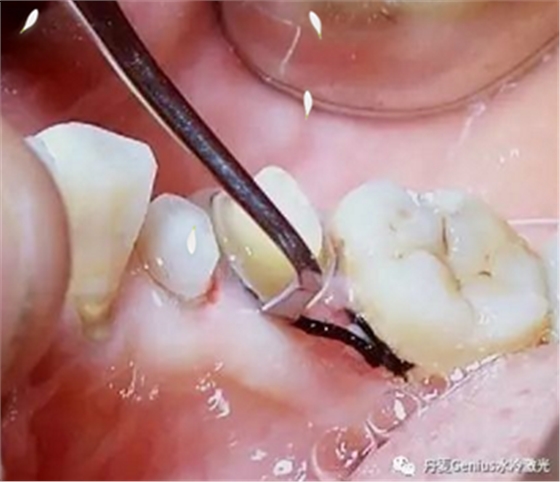

排齦-排齦操作前3分鐘,表麻涂抹于牙齦上,有效緩解剝離游離齦過(guò)程中產(chǎn)生的疼痛